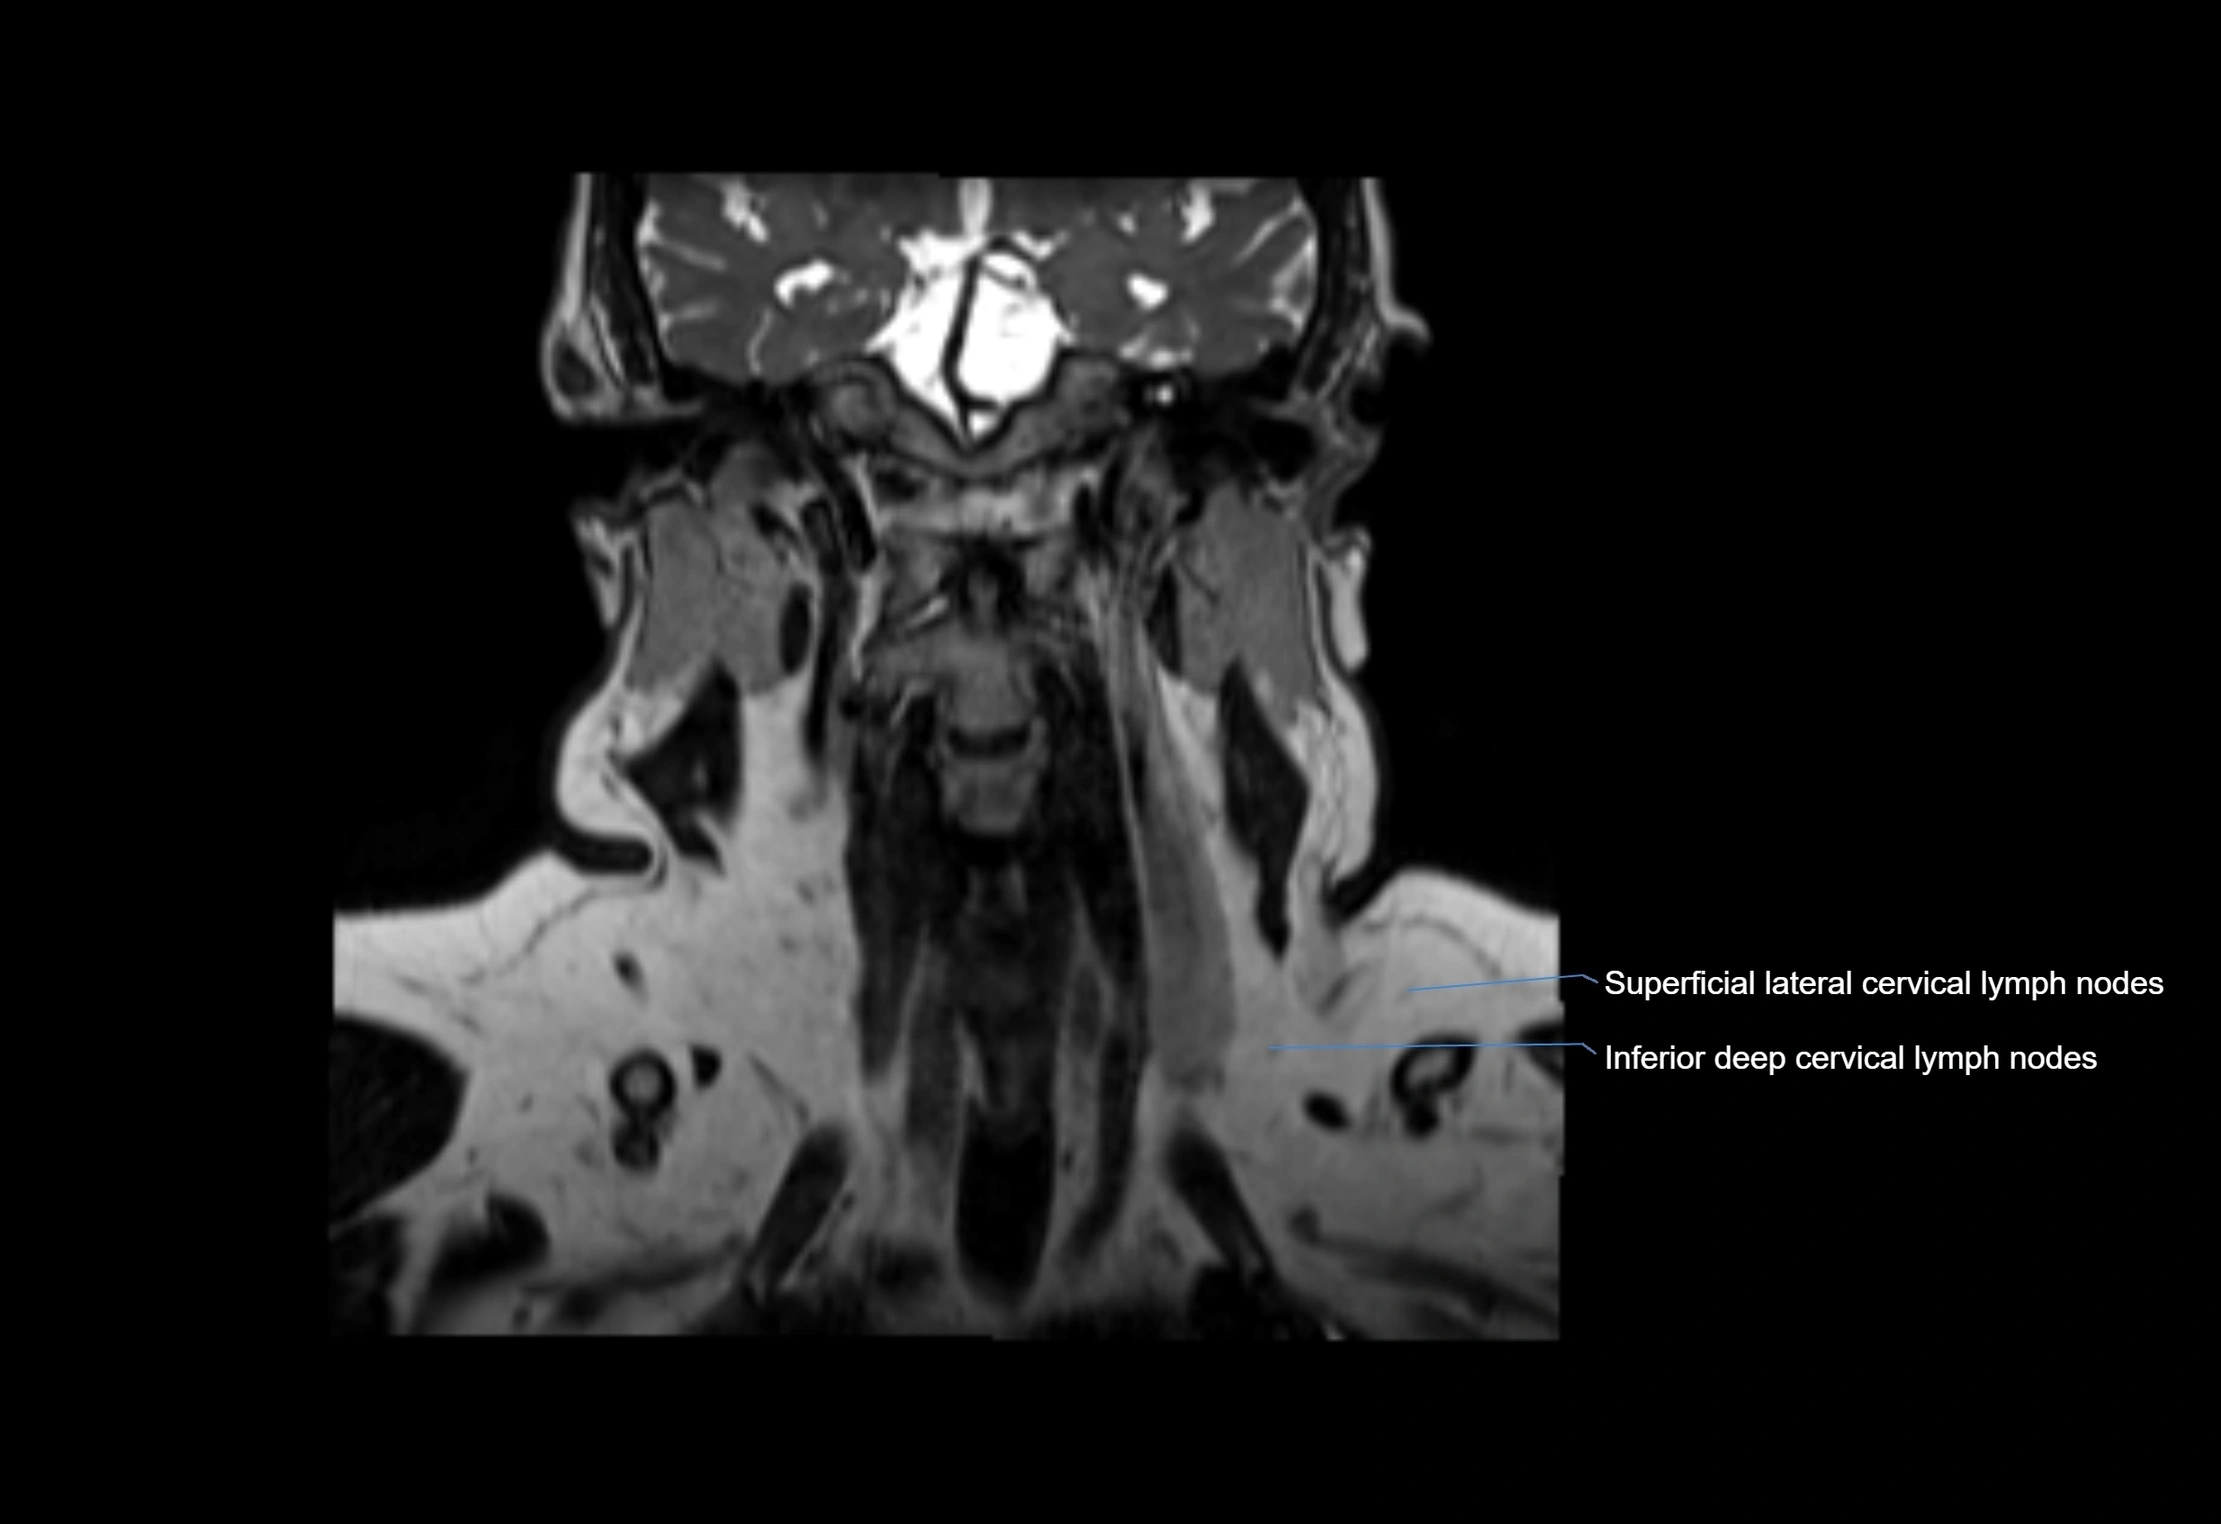

MRI Appearance

T2-weighted images:

• Nodes show intermediate signal, with surrounding fat bright

• Useful for detecting edema, inflammation, or infiltration

• Fatty hilum may appear slightly hyperintense relative to cortex

MRI images

image